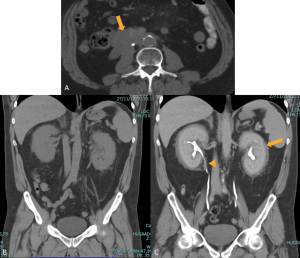

RPF typically appears as a well-defined, irregular paraspinal soft-tissue mass, isodense to the psoas muscle and without lateral extension beyond it. Most often centred at L4–L5 near the aortic bifurcation, it may extend cranially towards the renal hila or, less commonly, caudally to involve pelvic structures. Baseline Hounsfield units (HU) values and the diameter of the retroperitoneal tissue can assist in assessing inflammatory activity. [1,3,5-8]